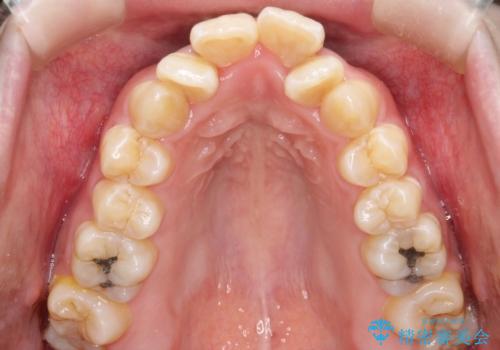

重度のガタガタ ワイヤーによる抜歯矯正

上下の歯に重度のガタガタがあり、前歯が下の歯と咬んでいない状態でした。

抜歯したスペースを使うことで、ガタガタと出っ歯を改善することができました。